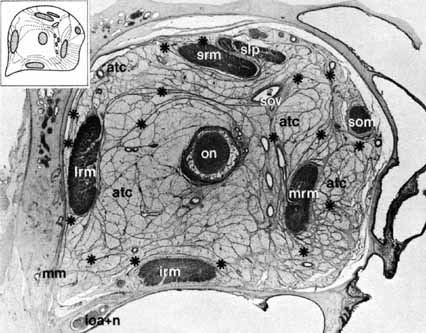

injury.  Fig. 13 Anatomic section demonstrating orbital septa 1.4 mm from behind the surface

of the eye. Diameters vertically, 2.4 cm; transversally, 2.7 cm. Enlargement

is approximately × 3.5. (ON, optic nerve; SOV, superior ophthalmic vein; SLP, superior levator palpebrae muscle; SRM, superior rectus muscle; LRM, lateral rectus muscle; IRM, inferior rectus muscle; MRM, medial rectus muscle; SOM, superior oblique muscle; *, connective tissue septa; ATC, adipose tissue

compartment; IOA + IN, infraorbital artery and nerve; MM, Müller's muscle) (From Koornneef L: Spatial aspects

of orbital musculofibrous tissue in man: A new anatomical and histological

approach. Amsterdam: Swets en Zeitlinger, 1976) Fig. 13 Anatomic section demonstrating orbital septa 1.4 mm from behind the surface

of the eye. Diameters vertically, 2.4 cm; transversally, 2.7 cm. Enlargement

is approximately × 3.5. (ON, optic nerve; SOV, superior ophthalmic vein; SLP, superior levator palpebrae muscle; SRM, superior rectus muscle; LRM, lateral rectus muscle; IRM, inferior rectus muscle; MRM, medial rectus muscle; SOM, superior oblique muscle; *, connective tissue septa; ATC, adipose tissue

compartment; IOA + IN, infraorbital artery and nerve; MM, Müller's muscle) (From Koornneef L: Spatial aspects

of orbital musculofibrous tissue in man: A new anatomical and histological

approach. Amsterdam: Swets en Zeitlinger, 1976)

|